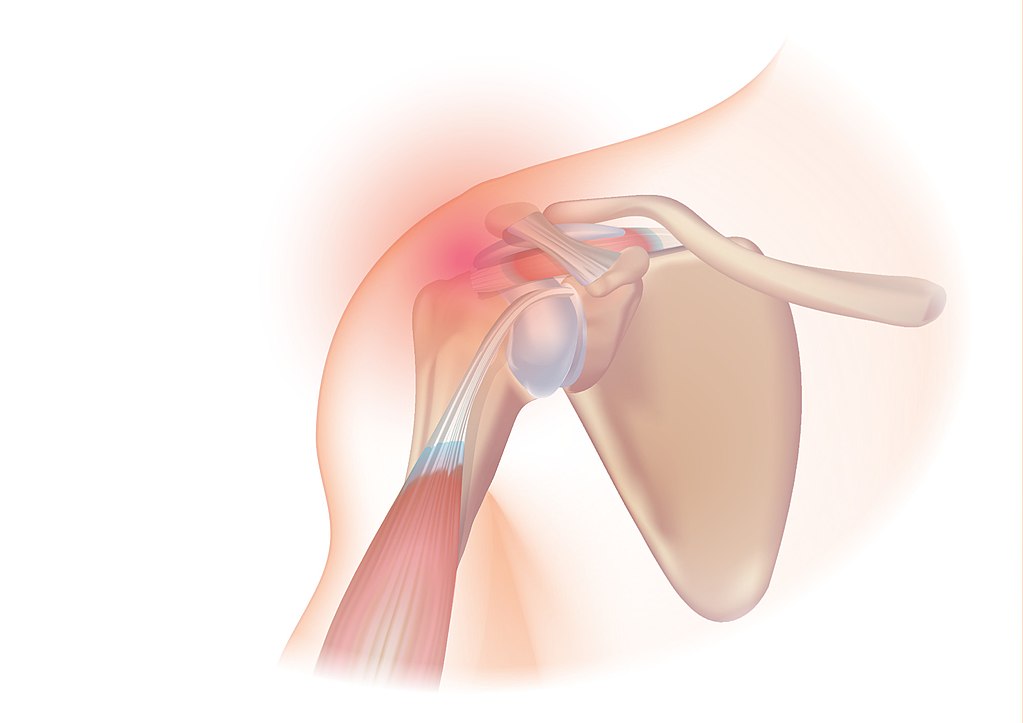

회전근개파열

어깨 회전근개의 근육(극상근, 극하근, 견갑하근, 소원근) 또는 힘줄 중 하나 이상이 파열되어 팔 또는 어깨에 통증을 유발하는 질환이다.

회전근개 파열(극상근 파열)

통증의 위치 그래픽